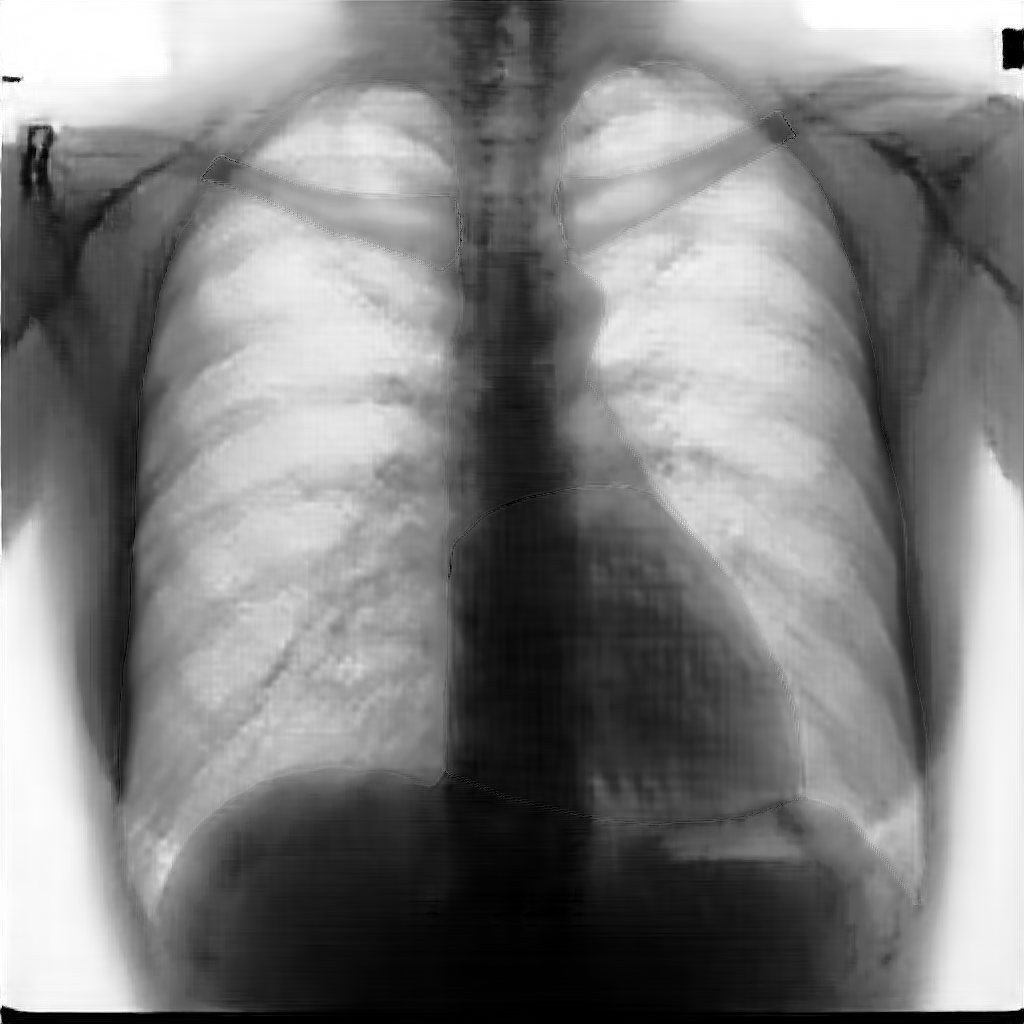

In this section, some examples of images and corresponding segmentations, generated with the approaches described in Section 3, are qualitatively examined. We also report some comments from three physicians on the generated segmentations, to provide a medical assessment of the quality of our method.

Figure 5 and Figure 6 display some examples — randomly chosen from all the generated images — of the label–maps and the corresponding chest X–ray images generated with the three methods described in Section 3, using the FULL_DATASET and the TINY_DATASET, respectively. We can observe that, with the single and two–stage methods, the images tend to be more similar to those belonging to the training set. For example, in most of the generated images there are white rectangles, which resemble those present in the training images, used to cover the names of both the patient and the hospital. Instead, the three–stage method does not produce such artifacts, suggesting that it is less prone to overfitting.

Moreover, in order to clarify the limits of the three–stage method, we assessed the quality of the segmentation results based on three human experts, who were asked to check 20 chest X–ray images, along with the corresponding supervision and the segmentation obtained by the SMANET network. Such images were chosen among those that can be considered difficult, at least based on the high error obtained by the segmentation algorithm. Figure 7 and Figure 8 show different examples of the images evaluated by the experts. The first column represents the chest X–ray image, while the second and the third columns, whose order was randomly exchanged during the presentation to the experts, represent the target segmentation and our prediction, respectively. The three physicians were asked to choose the best segmentation and to comment about their choice. Apart from a general agreement of all the doctors on the good quality of both the target segmentation and the segmentation provided by the three–stage method, surprisingly, they often chose the second one. For the examples in Figure 7, for instance, all the experts share the same opinion, preferring the segmentation obtained by the SMANET over the ground–truth segmentation. To report the results of the qualitative analysis, we numbered the target and predicted segmentation with 1 and 2, respectively, while doctors were assigned unordered pairs to obtain an unbiased result. Then, with respect to Figure 7(a), the comments reported by the experts were: 1) In segmentation 1, a fairly large part of the upper left ventricle is missing; 2) I choose the segmentation number 2 because the heart profile does not protrude to the left of the spine profile; 3) The best is No. 2, the other leaves out a piece of the left free edge of the heart, in the cranial area. Instead, for Figure 7(b), we obtained: 1) The second image is the best for the cardiac profile. For lung profiles, the second image is always better. The only flaw is that it leaks a bit on the right and left costophrenic sinuses. 2) Image 2 is the best, because the lower cardiac margin is lying down and does not protrude from the diaphragmatic dome. Image number 1 has a too flattened profile of the superior cardiac margin. 3) No. 2 for the cardiac profile more faithful to the real contours.